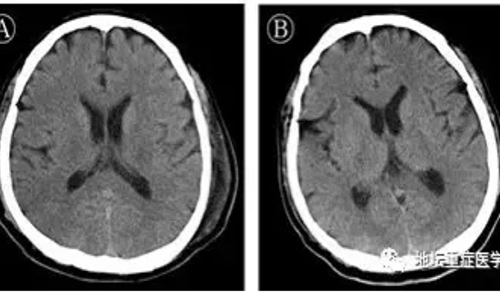

Photo: Wechat of ICU department of the Beijing Ditan Hospital

The patient recovered and was discharged from hospital on February 25. He was hospitalized one month earlier for respiratory failure. Doctors conducted gene sequencing on his cerebrospinal fluid as he showed symptoms of neurological disorder like twitching on the face after days of treatment while a CT scan and biochemical test results could identify the causes.